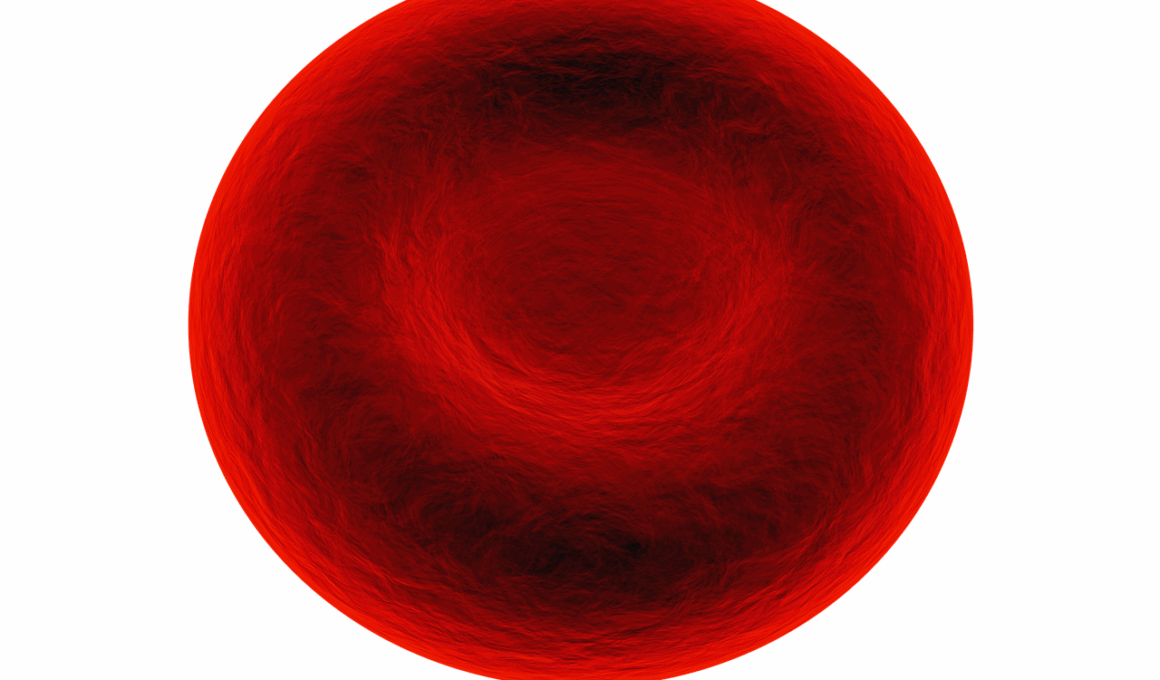

Feline anemia is a common yet serious health issue affecting many cats. It occurs when there are insufficient red blood cells in circulation, which can lead to inadequate oxygen supply to their tissues. Symptoms can often be quite subtle initially, making it crucial for cat owners to observe their pets closely. Common signs include lethargy, weakness, and difficulty breathing. Additionally, a cat with anemia might have pale gums or a rapid heartbeat. If you notice these symptoms, it’s essential to consult a veterinarian promptly. Blood tests can help determine anemia’s severity and underlying causes, such as parasites, chronic diseases, or nutritional deficiencies. Disclosure of any recent changes in the cat’s behavior or environment might aid the vet in forming a diagnosis. Treatment options vary based on the underlying issue but may include blood transfusions, medications, or dietary changes. Additionally, addressing any external parasites or infections might be necessary. Regular check-ups can help catch feline anemia early in otherwise healthy cats, preventing more severe complications. Cat owners should remain informed and proactive to ensure their pets remain happy and healthy.

Anemia in cats can manifest in several forms, primarily categorized into regenerative and non-regenerative types. Regenerative anemia occurs when the bone marrow responds to anemia by producing new red blood cells, signaling that the body is attempting to recover. However, in non-regenerative anemia, the bone marrow fails to produce sufficient red blood cells, leading to a more chronic condition. Understanding these distinctions is essential for cat owners. Various factors contribute to anemia’s onset, including underlying health conditions such as feline leukemia virus (FeLV) or feline immunodeficiency virus (FIV). Additionally, nutritional deficiencies like a lack of iron or vitamin B12 can further exacerbate the situation. A proper assessment by a veterinarian is vital in differentiating these forms and tailoring the treatment accordingly. Owners should provide their cats with a balanced diet that meets all nutritional needs. Regular screenings for infectious diseases are equally crucial, especially in multi-cat households. If anemia is suspected, immediate veterinary attention can mean the difference between a mild issue and a severe health crisis. Prompt diagnosis and treatment significantly improve a cat’s prognosis and overall well-being.